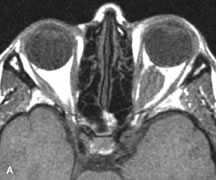

Extraocular muscle enlargement in patients with thyroid-associated orbitopathy is demonstrated equally well with CT and MRI studies. However, the superior tissue contrast on MR images reveals better details of the relationships of the optic nerve to the thickened muscles at the orbital apex (Fig. 16).50 In addition, MRI may be able to differentiate between muscles that are enlarged as a result of edema and active inflammation and those enlarged because of fibrosis by their T2 relaxation times.21 Quantitative MRI was not found to be accurate in predicting the success of low-dose orbital irradiation.51 However, a muscular index relating the diameters of the rectus muscles to the bony orbital dimensions was useful in predicting optic nerve compression.52

Fig. 16. A-C, T1-weighted MR scans obtained with a high-resolution surface coil demonstrate fusiform enlargement of the extraocular muscles. The medial, lateral, and inferior rectus muscles are especially involved. Note the relative sparing of the tendinous insertions, a finding characteristic of this disease process, as well as fatty infiltration of the lateral and inferior rectus muscles. There is marked proptosis, best visualized on the sagittal image (A), and mild crowding of the optic nerve at the orbital apex.